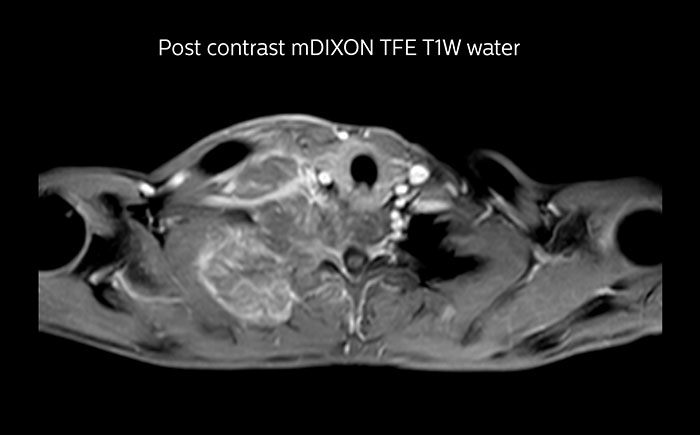

Although the area between the neck and the top of the lung is one of the most difficult areas for MRI, Prodiva 1.5T images show good quality in this 56-year-old male with Pancoast tumor on the right. mDIXON TFE images shows excellent fat suppression in the neck area and the DWI shows almost no distortion.